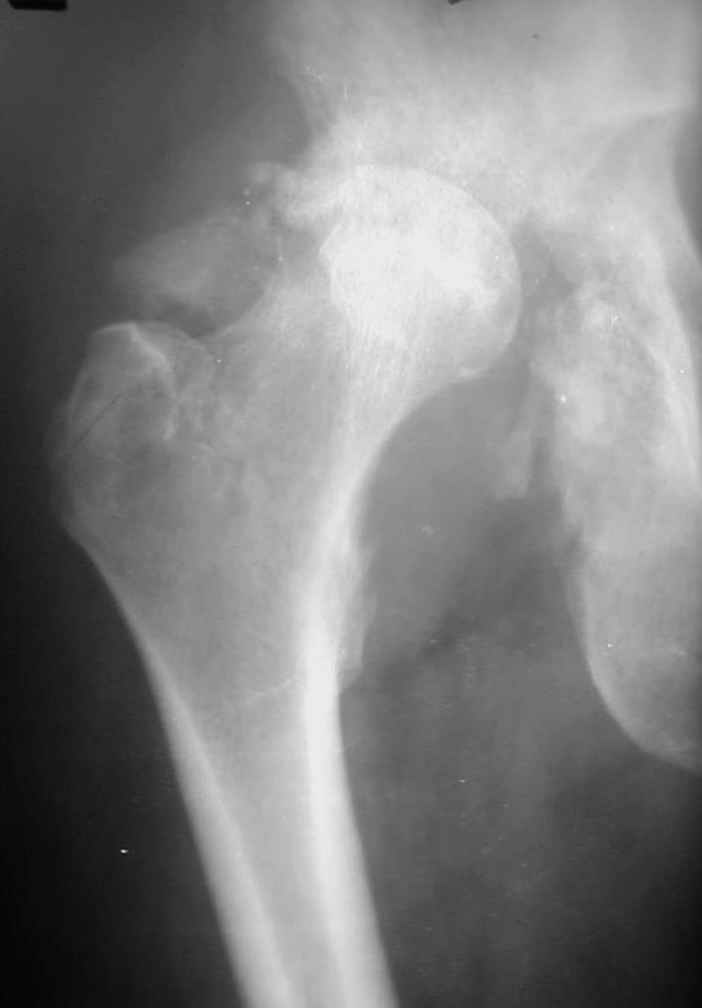

РАВ> Есть ли у Вас примеры установки протеза при обширных дефектах впадины?

РАВ> Какой был самый большой дефицит задней колонны, какой срок наблюдения,

РАВ> довольны ли Вы результатом?

РАВ> В предлагаемой ситуации имеется последствия перелома задней колонны,

РАВ> что значительно больше усугубляет ситуацию, чем банальный дефект

РАВ> заднего края, и костного материала из головки может просто не хватить,

РАВ> тем более что в таком случае как раз вся нагрузка должна лечь на эту

РАВ> несчастную костную пластику.